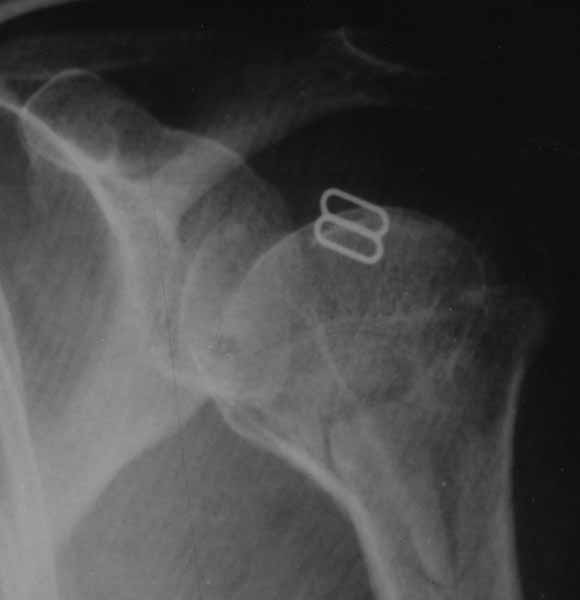

DS: Закрытый оскольчатый перелом шейки и головки левого плеча с удовлетворительным стоянием обломков |

Женщина 42 лет неделю назад упала на катке. В течение часа была доставлена в травмпункт где сделан R-снимки и наложен гипс от фаланг до середины спины. На след.день в траматологии снова R-снимки уже в гипсе и поставлен приведенный в теме диагноз. Через 5 дней еще R-снимки и осмотр по результатам поверх гипса наложена повязка Дезо. Сканированию поддается только приведенный снимок. По другой проекции сказано что стояние идеальное. Показано консерв.лечение по причине скученности и большого кол-ва осколков. Отправлены отдыхать 3 недели. Больная неделю не может спать лежа из-за ноющей тупой боли и гипс давит на живот. Сидя боль меньше но спать неудобно. На вопрос о возможности замены гипсовой лангетки на современный пластиковый "гипс" ответ врача отрицательный.Можно ли на основании приведенного снимка сделать заключение о правильности выбора метода консервативного лечения?

В этом случае надо сделать еще и КТ. Очень возможно, что тут есть проблемы, которые удастся решить операцией.

Вальгусный вколоченный перелом. Смещение некритичное, жить можно. Оперировать большой необходимости нет. Достаточно косыночной повязки на 4 недели.